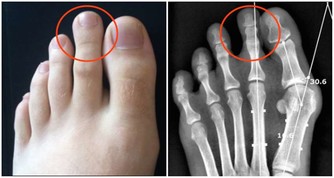

大腸癌的成因:「簡單說,是先有便祕,接著產生息肉,再病變成大腸癌。」大腸是由升結腸、橫結腸、降結腸及乙狀結腸等所構成,左側的大腸管徑比右 側大腸窄,當有腫瘤發生時,就會出現腸阻塞而引起便祕、腹脹甚至腹痛的情形。

因為糞便大多在左側的結腸成形,因此如果阻塞的狀況嚴重的話,所排出的糞便就 會有時還會參雜血絲, 嚴重到便祕及解血便情形。